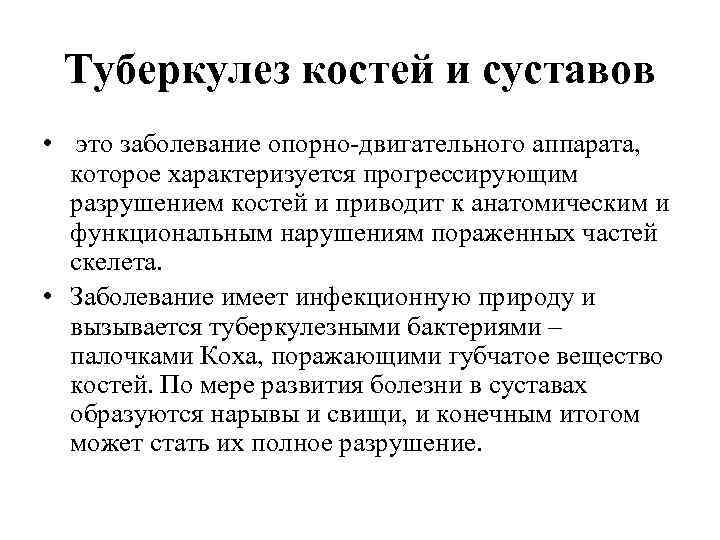

Туберкулез костей и суставов • это заболевание опорно-двигательного аппарата, которое характеризуется прогрессирующим разрушением костей и приводит к анатомическим и функциональным нарушениям пораженных частей скелета. • Заболевание имеет инфекционную природу и вызывается туберкулезными бактериями – палочками Коха, поражающими губчатое вещество костей. По мере развития болезни в суставах образуются нарывы и свищи, и конечным итогом может стать их полное разрушение.

Туберкулез костей и суставов • это заболевание опорно-двигательного аппарата, которое характеризуется прогрессирующим разрушением костей и приводит к анатомическим и функциональным нарушениям пораженных частей скелета. • Заболевание имеет инфекционную природу и вызывается туберкулезными бактериями – палочками Коха, поражающими губчатое вещество костей. По мере развития болезни в суставах образуются нарывы и свищи, и конечным итогом может стать их полное разрушение.